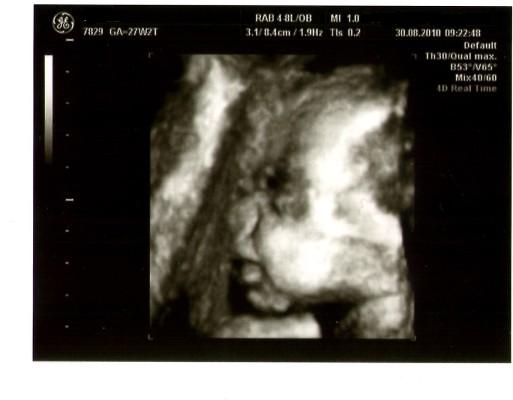

VU war super, Mia entwickelt sich völlig zeitgerecht und weiß auch was sich gehört, denn sie hat sich wieder in SL gedreht!

So und jetzt mal ein Bildchen von unserer Kleinen.